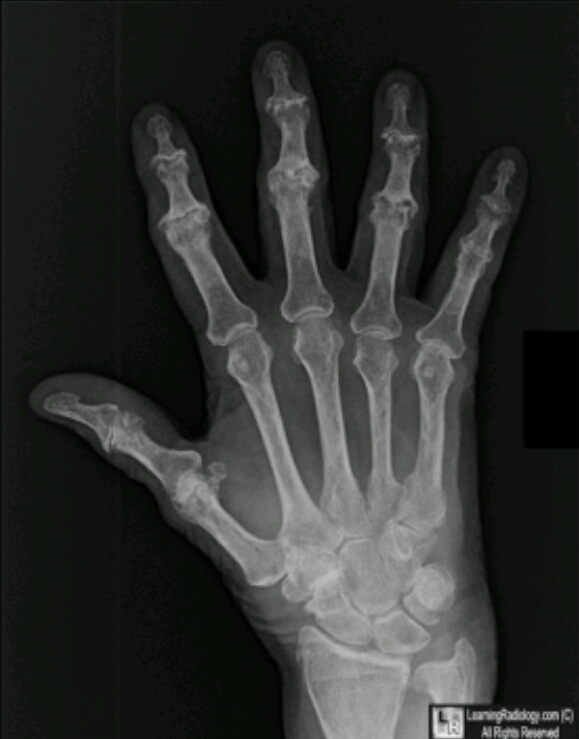

What disease is this? What are the features on this image of the disease?

DJD

DIP

PIP

1st MCP

subchondral sclerosis

osteophytes

cystic changes

loss of joint space

misalignment